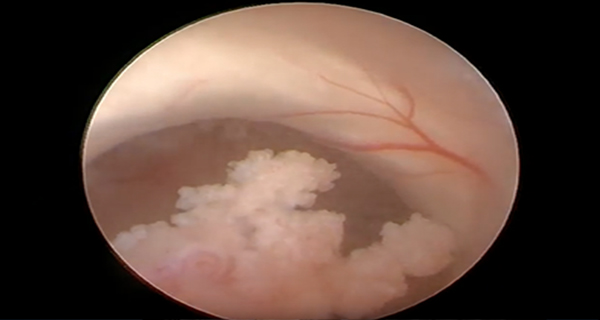

endoscopic view

Endoscopic Third Ventriculostomy Surgery